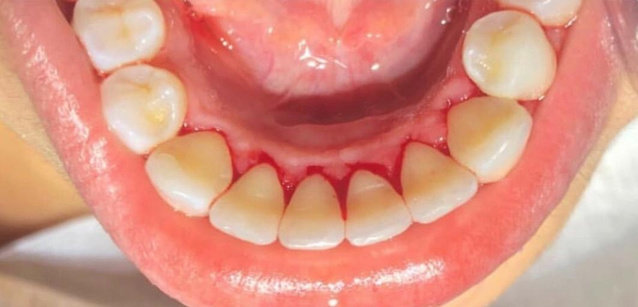

resina composta em dente anterior

curso de restaurações estéticas em resina composta

realidade clínica: resina composta